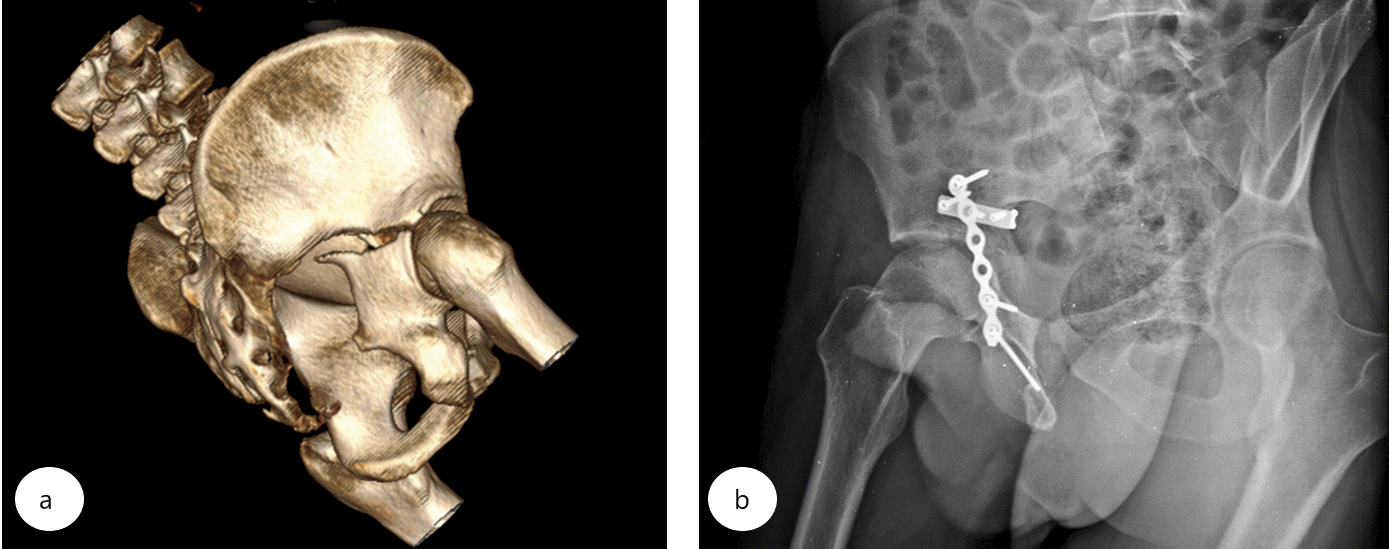

Пациент 27 лет пострадал в результате ДТП (водитель). Через три недели было выполнено оперативное вмешательство по поводу юкстатектального поперечного перелома правой вертлужной впадины с преимущественным смещением в области задней колонны и медиальным подвывихом головки бедра (рис. 2 а).

В положении пациента на боку выполнен классический задний доступ к вертлужной впадине по Kocher – Langenbeck. Попытка провести репозиционный маневр с помощью больших щипцов Jungbluth с винтами 4,5 мм оказалась неэффективной из-за «вырывания» якорного винта из дистального отломка. С первой попытки выполнены успешная репозиция с помощью разработанного способа и фиксация достигнутого положения 1/3 трубчатой пластиной с угловой стабильностью Synthes (рис. 2 б). Затем выполнен окончательный остеосинтез задней колонны нейтрализующей тазовой пластиной Matta (Stryker) и кортикальными винтами 3,5 мм.

Рис. 2. Поперечный юкстатектальный перелом правой вертлужной впадины со смещением (AO/OTA 62B1.2): а — 3D-реконструкция КТ таза; b — послеоперационная рентгенограмма правой вертлужной впадины в косой подвздошной проекции по Judet